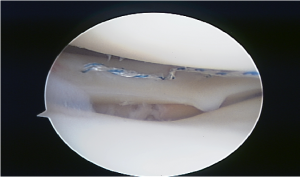

All inside meniscal fixation using mainly two FasT-Fix® devices (Smith and Nephew)

All inside meniscal fixation is a successful treatment in this largest case series published of HLM